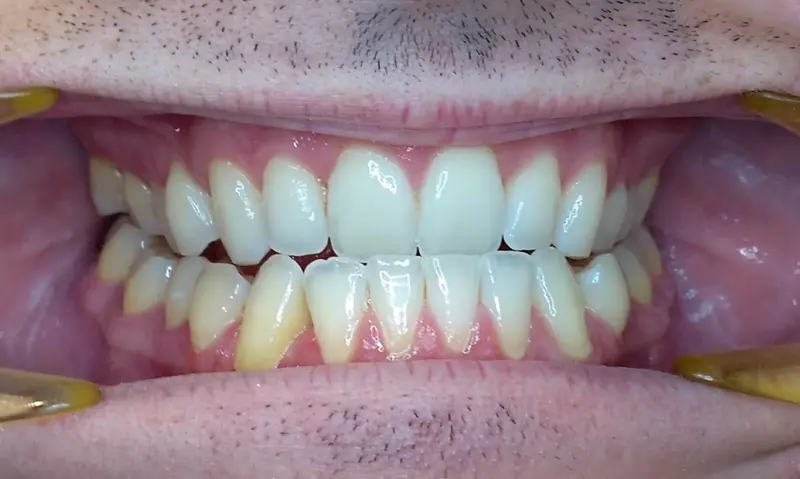

The Diagnosis

Bimaxillary protrusion (teeth flaring forward) causing lip incompetence. The patient struggled to close his lips comfortably, straining the chin muscle (mentalis).

The Engineering

A strategic extraction plan (4 premolars) allowed us to retract the front teeth. Note the dramatic improvement in chin projection and facial balance. The extractions did not flatten the face; they harmonized it.